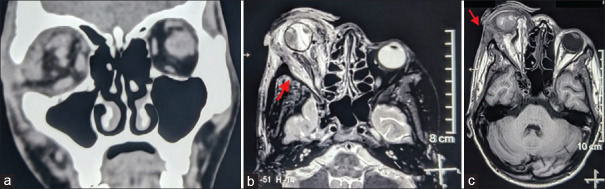

颈动脉海绵窦瘘(CCF)是一种罕见的疾病,涉及颈动脉和海绵窦之间的异常沟通。我们介绍了一例独特的创伤后单侧 CCF 病例,患者最初被误诊为角膜熔化并伴有虹膜脱垂和眼眶蜂窝组织炎。患者是一名 25 岁的男性,摔倒后患眼肿胀、出血,视力突然下降。影像学检查证实患者患有直接CCF,患者接受了血管内卷曲术、剥离术和人工晶体置换术。术后观察到部分睑上提肌功能丧失。该病例凸显了CCF在诊断方面的挑战,并强调了早期准确诊断对适当治疗的重要性。

Carotid-cavernous fistula (CCF) is a rare condition involving an abnormal communication between the carotid artery and the cavernous sinus. We present a unique case of posttraumatic unilateral CCF initially misdiagnosed as a corneal melt with iris prolapse and orbital cellulitis. The patient, a 25-year-old male, experienced swelling, bleeding, and sudden vision loss in the affected eye following a fall. Imaging confirmed a direct CCF, and the patient underwent endovascular coiling, evisceration, and prosthetic replacement. Partial loss of levator palpebrae superioris muscle function was observed postprocedure. This case underscores the diagnostic challenge of CCF and highlights the significance of early and accurate diagnosis for appropriate management.